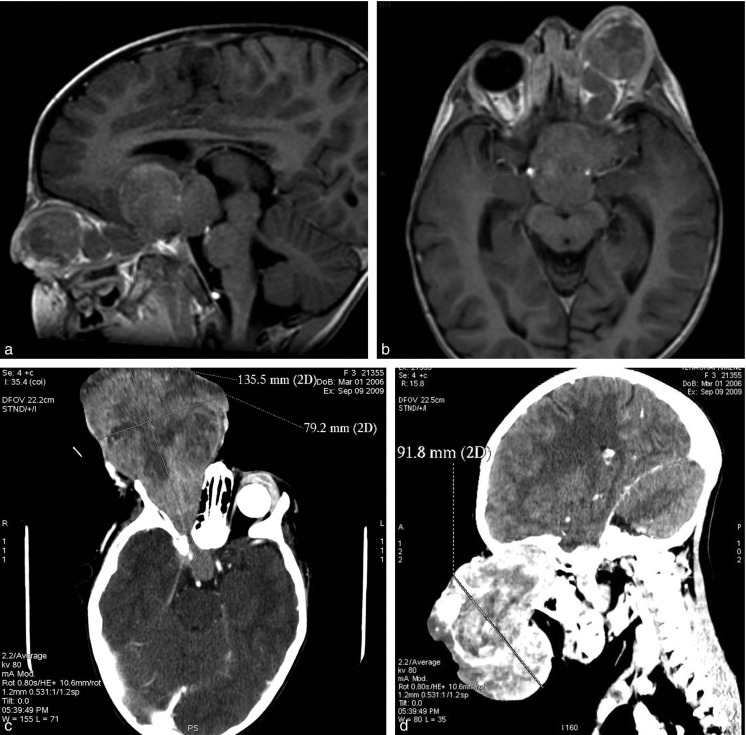

Traitement non conservateur